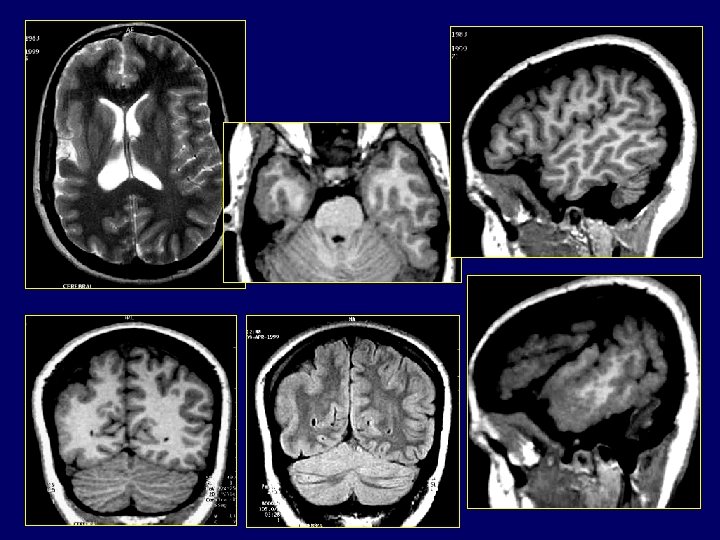

Malformations liées à une anomalie de La migration neuronale Lissencéphalie / arrêt de la migration neuronale avec cortex à 4 couches Aspect IRM caractéristique : – – – – Surface cérébrale lisse: absence totale de sillons SB réduite et cortex épais avec absence d’inter digitations CC petit Vallée sylvienne ouverte et verticalisée (immature) Calcifications possibles Cervelet normal Lissencéphalie liée à l’X , bande d’hétérotopie chez la fille. Pachygyrie: Lissencéphalie incomplète où seuls les principaux sillons présents. Anomalies diffuses ou localisées Agyrie : Lissencéphalie complète

Malformations liées à une anomalie de La migration neuronale • Héterotopies Aspects typiques ( différencier de la STB, gliose): – Signal: substance grise. – Forme: nodulaire, laminaire, “cortical infolding”. – Distribution: isolées/multiples/diffuses, uni- or bilatérales, symétriques ou pas; topographie lobaire. – Localisation: périventriculaire, sous-corticale, transcérébrale.

Classification: - nodulaire (dispersées, diffuses) périventriculaires; nodulaires sous-corticales; laminaires sous-corticales (en bande); lissencéphalies (agyrie-pachygyrie).

Hétérotopie nodulaire • Bilatérales et diffuses: X-linked, lethal chez le mâle (FLN 1). • Cortex réduit.

Hétérotopies nodulaires sous-corticales • Volumineux amas de SG • Continus avec le cortex, • Ventricule localement dilaté Substance blanche et LCR mêlés.

Hémi-mégalencéphalies • Étiologies et aspects très variés. Peuvent se voir dans : – – – Hémi-hypertrophie homolatérale Syndrome Proteus Hypomelanose d’Ito NF type I STB – – – Zônes pachygyriques Polymicrogyries Hétéretopies Balloon cells Astrogliose de la SB • Associent de façon variable

Hémimegalencéphalie aspects en IRM • Diagnostic facile en IRM – Ventricule homolatéral large, à cornes étirées – Cortex épais à gyrus larges et sillons courts – Jonction SB – SG floue – Souvent hypersignal de la SB